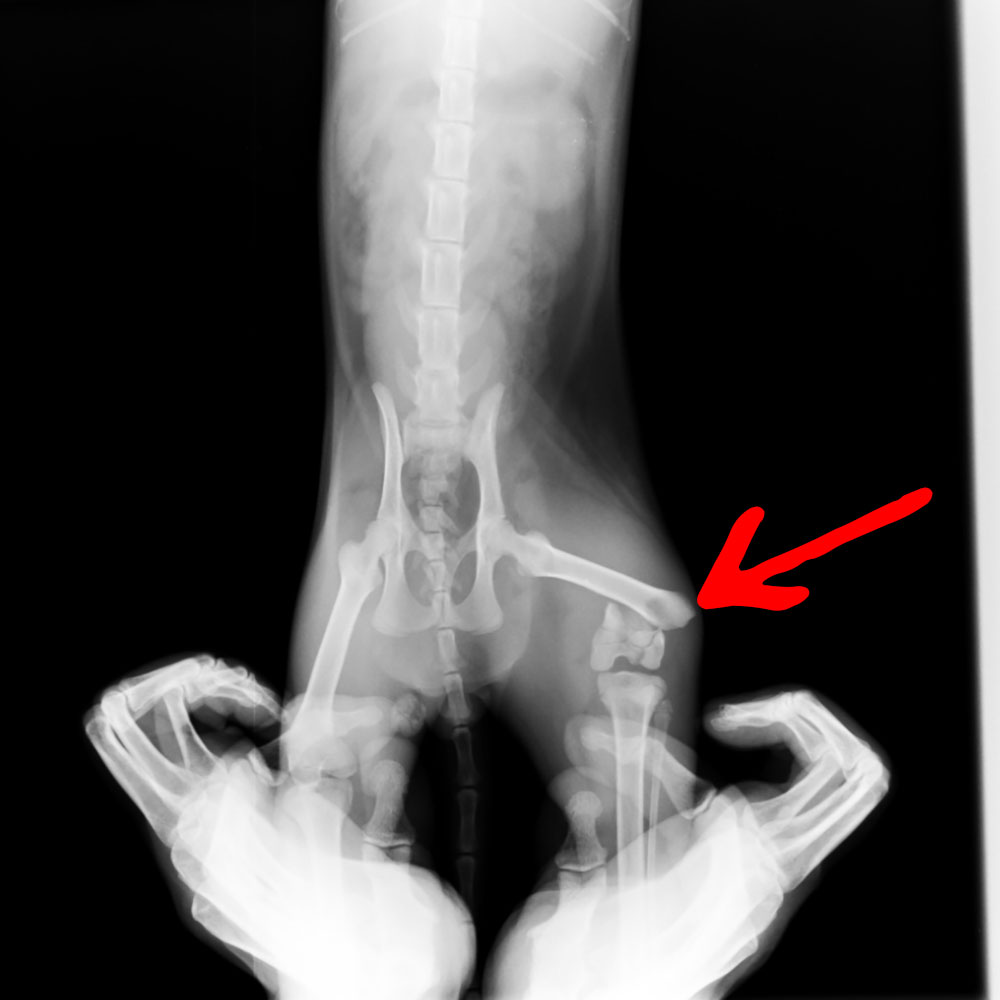

左足大腿骨が完全にポッキリ折れていて、手術となりました。

レントゲンの結果、今は9割くらい骨がくっついてきている良好な状況で、歩行等に問題が無くなってきましたので里親さんを募集いたします。